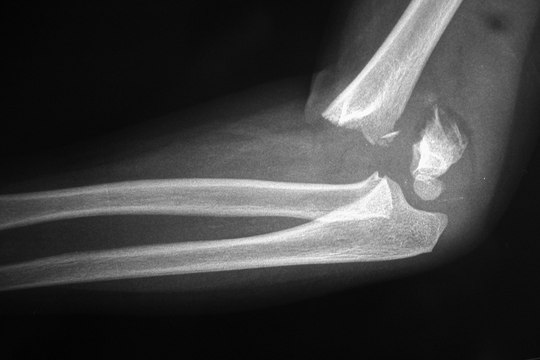

Fracturas. Tratamientos en columna vertebral. Prótesis.

Fracturas, Tratamientos, columna, vertebral, Prótesis